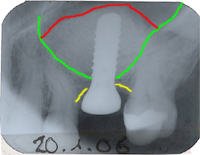

Ich habe die Situation mit dem Patienten besprochen und ihm angeraten, denselben Eingriff nach einer gewissen Abheilungszeit der Sinusschleimhaut nochmals vorzunehmen. Den zweiten Sinuslift habe ich am 20. Januar 2006 vorgenommen und wie Abb. 2 zeigt, erfolgreich. Da in diesem Fall nur mit Knochenersatzmaterialen gearbeitet wurde, die ca. ein Jahr brauchen, bis sie der Organismus zu Eigenknochen umbaut, konnten wir die Überkronung dieses Implantates erst ein Jahr nach dem Sinuslift machen.

Bereits elf Monate nach dem Sinuslift konnte die Porzellankrone auf dem Implantat zementiert werden (Abb. 4). In Abb. 3 sieht man das dazugehörende Röntgenbild nach dem Zementieren der Krone.